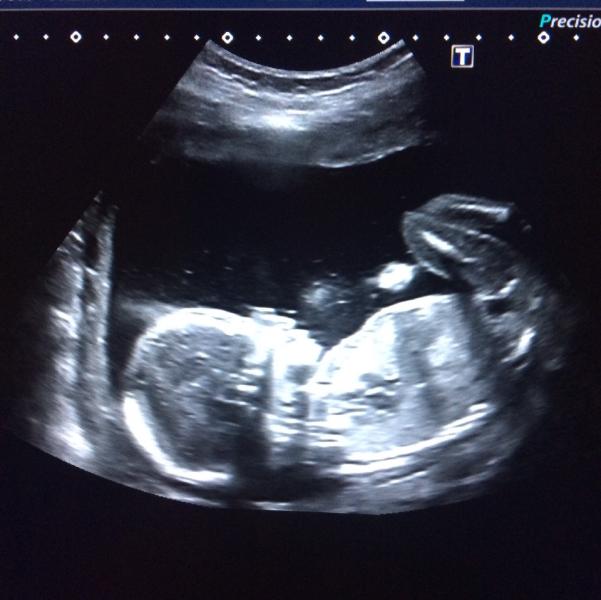

Второй скрининг пройден .с малышом все хорошо.опережает на 3 дня срок.оказался ну крайне скромным и не показал нам своё местечко интересное😔а вот проблема с моей гематомой,опять она 66 на 24 мм.теперь еще и участок с неоднородностью плаценты😱😱было у кого такое дело?узист просто говорит сдай на инфекции мазок и никаких тяжестей..а ну и без интима 🙄